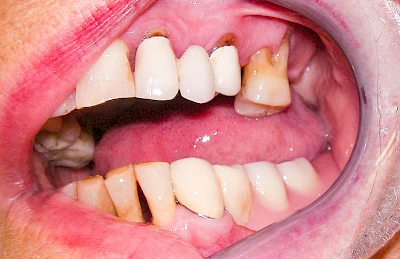

Gingivitis & Parodontitis: Stadien

Ist zunächst nur das Zahnfleisch von der Entzündung betroffen, spricht man von Gingivitis. Später, wenn auch der Knochen um die Zähne herum entzündet ist, spricht man von einer Parodontitis. Bei der Parodontitis wird der Knochen nach und nach abgebaut und das Zahnfleisch zieht sich zurück. Die Zahnhälse und Zahnwurzeloberflächen liegen mehr und mehr frei. Die Zähne werden zunehmend lockerer und fallen schließlich aus.

Bei Implantaten – also operativ eingebrachten künstlichen Zahnwurzeln – kann der Körper die Bakterien auch nicht so gut abwehren. Hier spricht man im Fall einer Entzündung von einer Peri-Implantitis, also einer Entzündung um das Implantat herum.